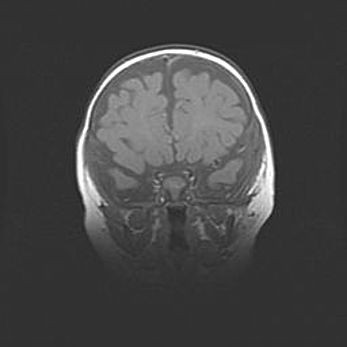

Лейкомаляция с кистозно-глиозной дегенерацией головного мозга.

Возраст: 2 месяца 25 дней

Вес: 6400 г

Окружность головы: 40 см

Срок гестации: 41 неделя

Лейкомаляцию относят к ишемически-гипоксическим повреждениям головного мозга, диагностируемым у новорожденных. При лейкомаляции в головном мозге обнаруживают очаги некроза, возникшие после тяжелой гипоксии и нарушения кровотока. В процессе морфогенеза очаги проходят три стадии: 1) развития некроза, 2) резорбции и 3) формирования глиозного рубца или кисты. Перивентрикулярная лейкомаляция (ПЛ) встречается примерно в 12% случаев среди новорожденных, обычно – у недоношенных детей, причем, частота ее зависит от массы, с которой младенец появился на свет. Наибольшее число малышей страдает лейкомаляцией, если масса при рождении 1500-2500 г.